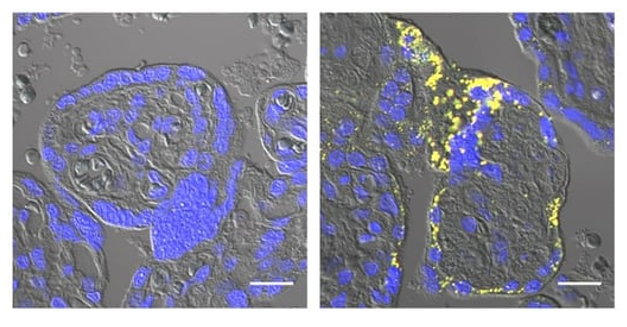

Amyloid-β aggregates (yellow) are present in preeclamptic (right) but not healthy (left) placentas. Credit: © 2026 Nishioka et al. Originally published in Life Science Alliance. Story by Dr Joe Milton, Australian Science Media Centre

Several previous studies including Buhimschi et al, 2014, Cater et al, 2019, and Cheng et al, 2021, have reported the presence of amyloid-β aggregates in preeclamptic placentas. Why amyloid-β accumulates under these conditions, and whether this impacts placental function and the development of preeclampsia, was unknown.

Hypoxia is known to inhibit a critical step in placenta formation known as syncytialization. During this step, placental stem cells fuse together to form the syncytiotrophoblast, the outer, multinucleated layer of the placenta that protects the developing fetus, produces crucial pregnancy hormones, and mediates the exchange of nutrients, gases, and waste between the mother and the fetus. Nishitsuji and colleagues found that amyloid-β aggregates impair the ability of placental cells grown in the lab to undergo syncytialization. In utero, this would likely inhibit syncytiotrophoblast formation and contribute to the development of preeclampsia.